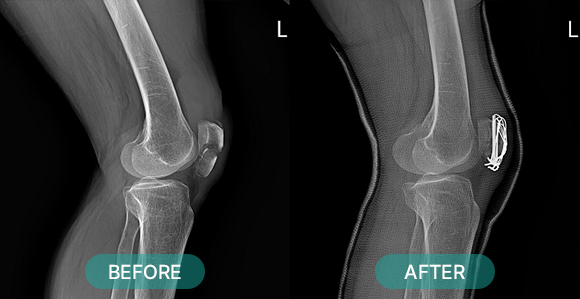

관혈적 정복이란 골절된 부위를 절개하고 뼈를 노출시켜 눈으로 직접 보면서 골절편을 정확하게 맞추는 방법으로 금속판과 나사 고정법, 핀고정법, 나사고정법, 골수 내정 고정법, 인공 관절 치환술, 외고정 기구 고정법 등등 여러 방식이 있습니다.

- 반월상 연골 절제술 및 봉합, 퇴행성 관절염

- 전/후방십자인대 파열 , 반월판 파열